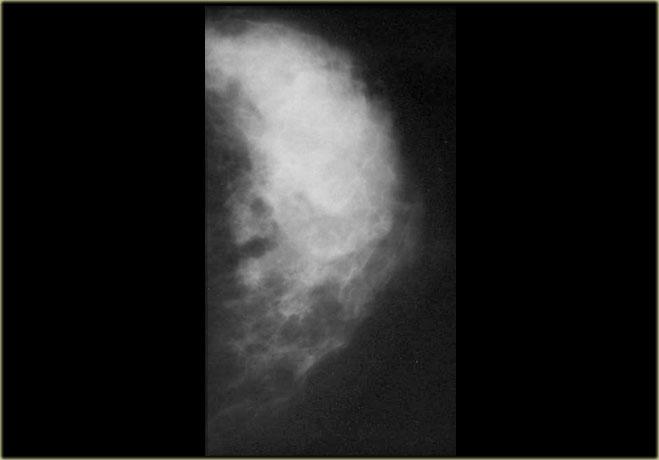

Bên trái là hình chụp nhũ ảnh vú nam giới với dạng gynecomastia thể nốt tuyến.

Có một vùng đậm độ hình quạt tỏa ra từ núm vú.

Tổn thương có thể nổi bật hơn ở góc phần tư trên ngoài và, quan trọng hơn, nó hòa lẫn vào mô mỡ xung quanh.

Nếu nhìn nhũ ảnh bên trái như là vú của một phụ nữ thay vì đàn ông, bạn có thể nhận định đây là một khối bờ không rõ và kết luận đây là tổn thương ác tính.

Tuy nhiên, ở nam giới, bờ không rõ này lại là dấu hiệu của gynecomastia.

Gynecomastia là sự tăng sinh đồng thời của các ống tuyến và mô đệm mà không có bao xơ bao quanh, do đó tổn thương phải hòa lẫn vào mô mỡ xung quanh.